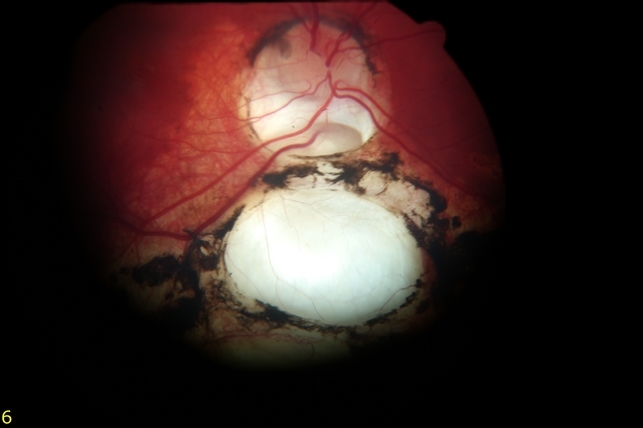

Atlas Entry - Chorioretinal Coloboma

Coloboma ocular oxford. Optic coloboma showing retcam lacunae